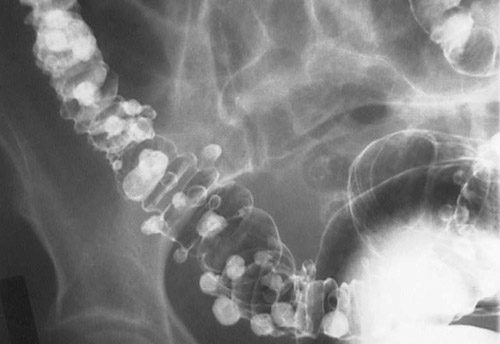

| Another barium enema with air contrast seen above and below reveals extensive colonic diverticulosis with numerous air and contrast-filled outpouchings from the colon. Stool impacted into the diverticula may erode small arteries at the margin, leading to bleeding. |